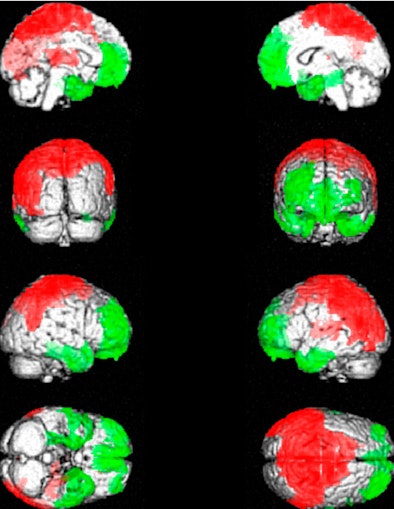

| The images show the anatomical localization of peak significant differences between brain SPECT of patients with fibromyalgia and healthy subjects. Patients with fibromyalgia exhibited posterior hyperperfusion (red), including of the somatosensory cortex, and hypoperfusion (green) of frontal, cingulate, temporal, and cerebellar cortices. Images courtesy of the Journal of Nuclear Medicine. |

Compared with healthy controls, patients with fibromyalgia exhibited posterior hyperperfusion, including of the somatosensory cortex, and hypoperfusion of the frontal, cingulate, temporal, and cerebellar cortices in particular, the temporal hypoperfusion including the polar and mediobasal cortices.